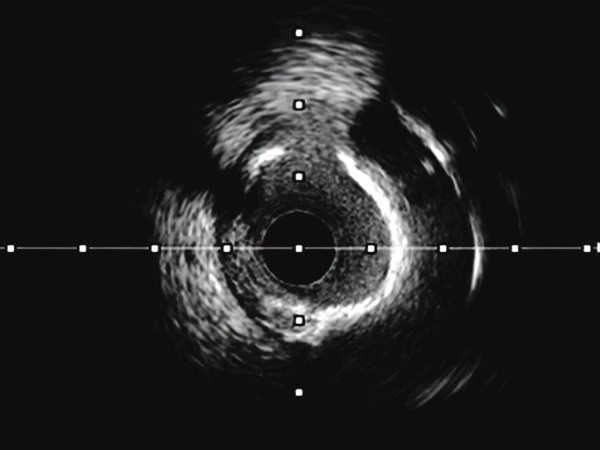

IVUS Guidance

IVUS use is critical to see, prep and treat all lesions in complex PCI treatment.

IVUS Guidance optimizes coronary outcomes. The complete Modern PCI toolkit is backed by data you can trust.